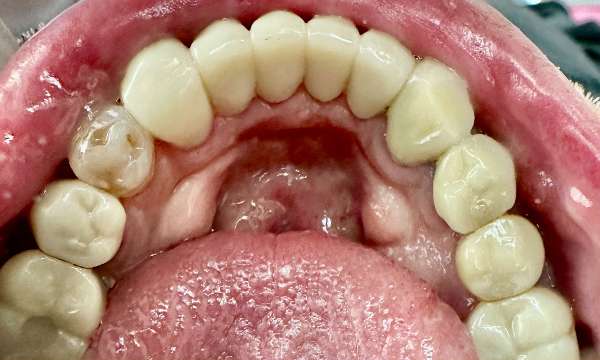

Fixing Broken Teeth

This patient came to us with broken teeth. Dental crowns gave them a more aesthetic appearance and improved their oral health.